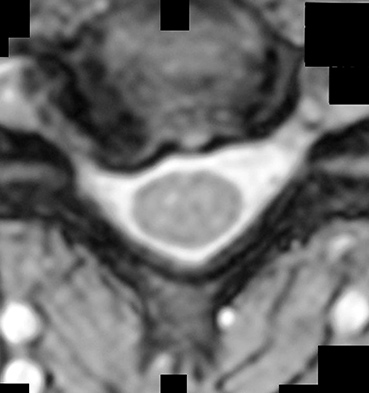

Figures 1 and 2 show sagittal and axial MRI from an 83-year-old woman with an ataxic gait, loss of dexterity, and intermittent loss of bowel and bladder control. The symptoms have been getting progressively worse over the past several weeks.

What disease process is most likely the cause of the patient’s symptoms?

4. Pigmented villonodular synovitis Discussion: B

The patient has a pannus at the C1-2 articulation that is compressing the spinal cord and causing myelopathy symptoms. The development of a pannus at this location has been associated with rheumatoid arthritis. Steinberger and associates showed increased morbidity and mortality when using an anterior approach and the surgery took longer than 4 hours. Chieng and associates showed better outcomes and lower complications rates using a posterior approach.

CLINICAL SITUATION

When discussing anterior versus posterior surgical techniques, you counsel this patient that

Discussion: A